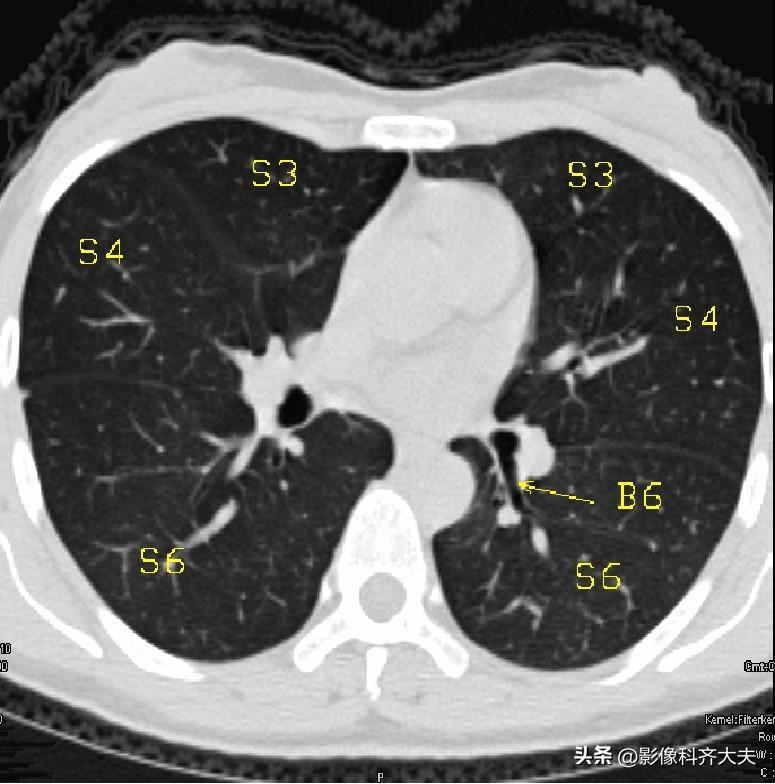

图12

▲B6:下叶背段支气管